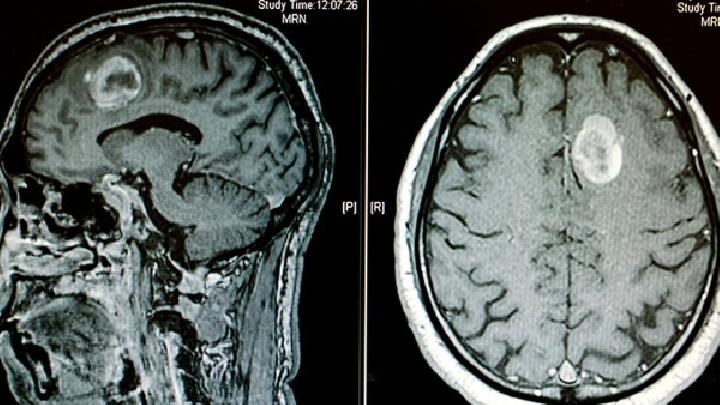

侧脑室肿瘤的症状是什么?我们可以从哪些症状来判断我们患有侧脑室肿瘤?接下来,让我们了解一下侧脑室肿瘤的相关症状。这样,当出现相关症状时,我们可以及时到医院进行相应的检查和治疗。